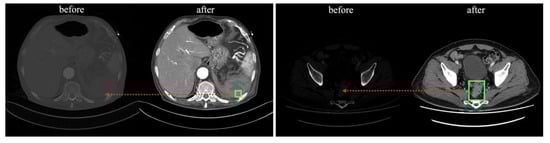

The processed images were normalized so that each pixel was linearly stretched by fitting a value between 0 and 1, and stored as a 512 × 512 pixel NumPy format array. The location of the lesion (green box) and structures, such as various organs in the abdomen are more visually distinct (red arrows) compared with the pre-processed images in Figure 2.

Figure 2. Comparison of before and after processing of DICOM file.